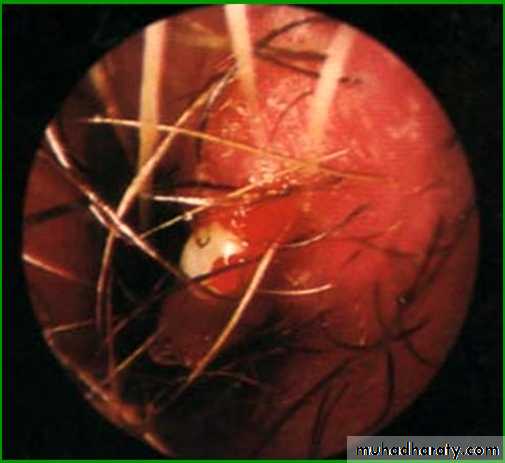

(Little’s area). Or “Kieselbach's plexus

This area is a common site for epistaxis (bleeding from the nose).Paranasal sinuses